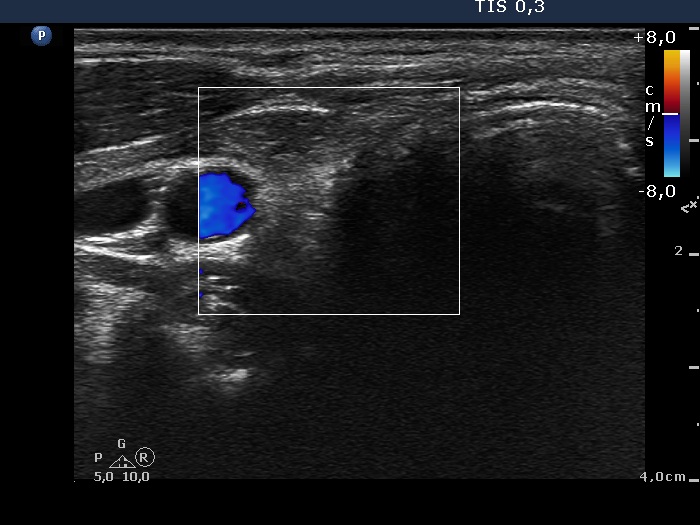

Follow-up investigation 11 months after surgery (ultrasonographic picture 3)

Right lobe, transverse scan, color Doppler mode. There is no vascularization in the thyroid bed.